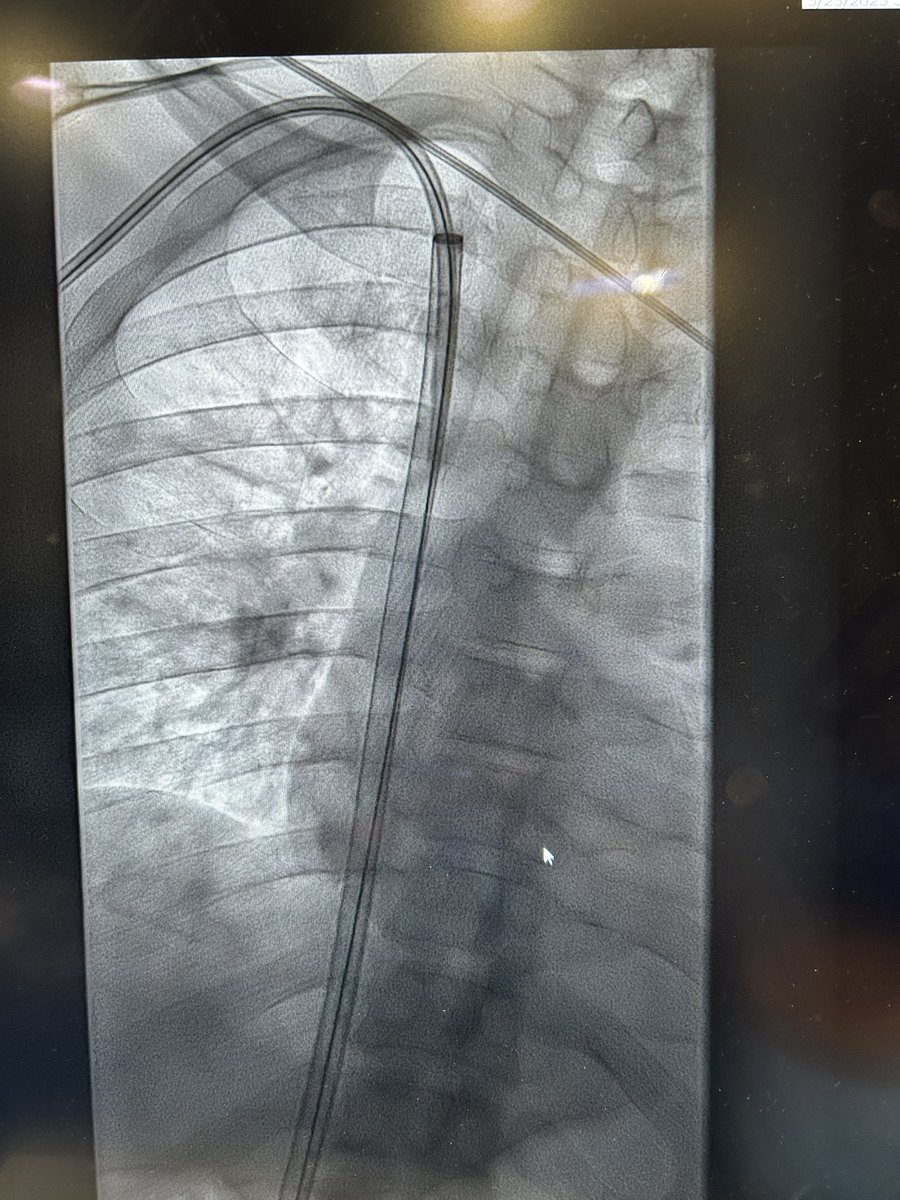

Case 75: with @BhaveshPopat7 . Intranodal Lymphangio(INL)+Thoracic Duct Embo(TDE): coil+glue for chylous pericardium sec to ALL . #irad #medtwitter #cardiotwitter @SriniTummala @TheRealDoctorOs @keithppereira @FadiSaab17 @t_intheleadcoat @SRajesh_IR @IR_Juniors @iRadBIR_Chennai